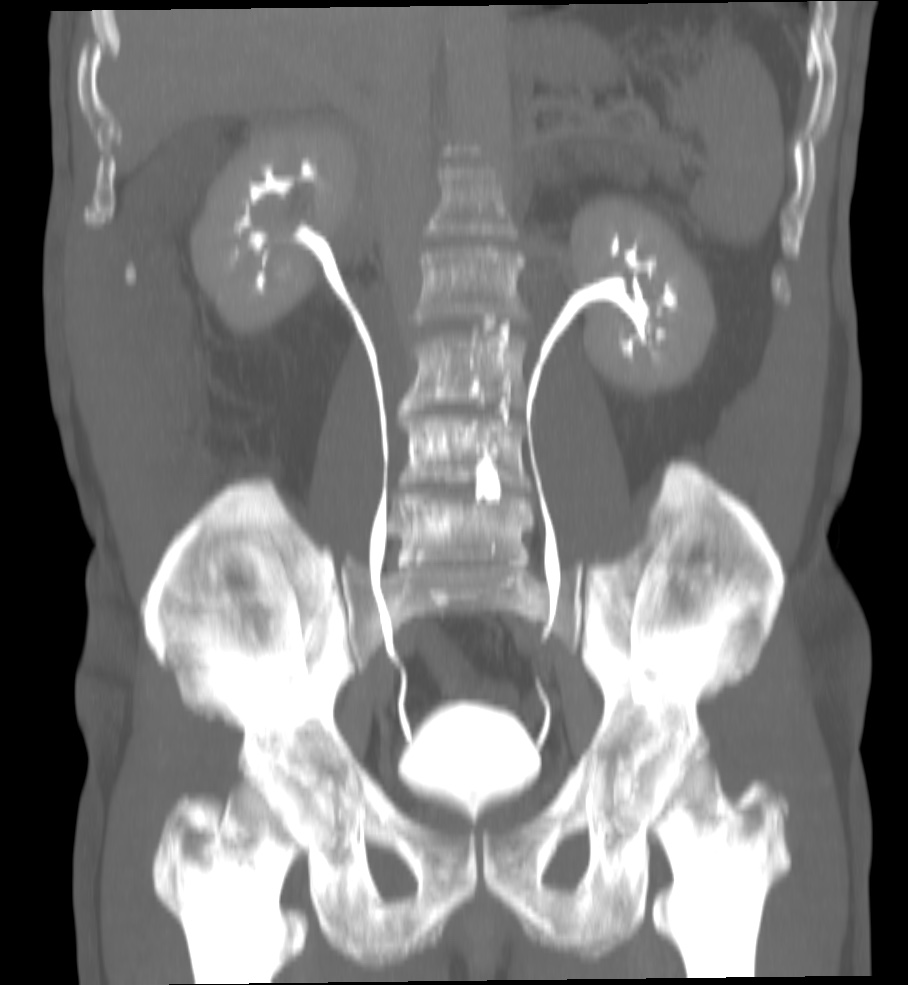

4. FIBROSIS.

Es un proceso inflamatorio y fibrótico que suele afectar el retroperitoneo central, afectando la aorta y la cava por delante. Es de localización infrarrenal, suele empezar por debajo de la bifurcación aórtica y desde ahí asciende. Secundariamente, puede englobar los uréteres pudiendo ocasionar hidroureteronefrosis. Se diferencia del linfoma en que NO produce desplazamiento anterior de la aorta.

Sin embargo, ocasionalmente puede extenderse más lejos y más lateral, afectando el espacio perirrenal. Hay una forma de fibrosis perirrenal que envuelve ambos riñones y se manifiesta como una banda densa alrededor de éstos que puede simular un linfoma.

Imagen en TC: Tejido con densidad de partes blandas, irregular y confluente, que en el caso de afectación del EPR puede rodear los riñones.